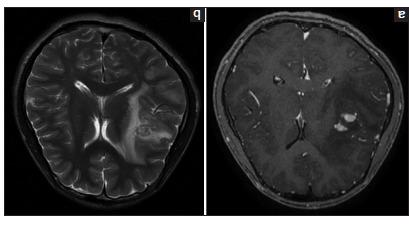

We report the case of a 16-year-old male who presented with persistent headaches and recurrent seizures despite adherence to antiseizure medications. Neuroimaging findings suggested an infectious process but were inconclusive in differentiating between a tuberculoma and cerebral schistosomiasis. Given the differing therapeutic approaches required for these conditions, a definitive diagnosis was pursued through a brain tissue biopsy, which confirmed cerebral schistosomiasis. This diagnosis guided appropriate treatment, leading to clinical improvement.

我们报告了一名16岁男性患者的病例,尽管坚持服用抗癫痫药物,但仍出现持续性头痛和反复癫痫发作。神经影像学检查结果提示存在感染性病变,但在鉴别结核瘤和脑血吸虫病方面尚无定论。鉴于这两种疾病所需的治疗方法不同,通过脑组织活检进行了明确诊断,结果证实为脑血吸虫病。这一诊断指导了恰当的治疗,使临床症状得到改善。